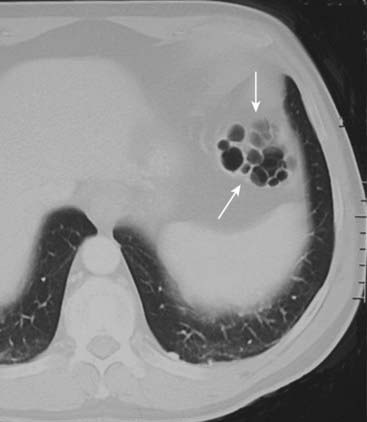

A rare, primary form called pneumatosis cystoides intestinalis, which usually affects the left colon, producing cystlike collections of air in the submucosa or serosa (Fig. 15-13).

Chronic obstructive pulmonary disease—presumably secondary to air from ruptured blebs dissecting through the mediastinum to the abdomen.

Figure 15-13 Pneumatosis cystoides intestinalis.

Axial CT scan of the upper abdomen windowed for lung technique shows a cluster of air-containing cysts (solid white arrows) associated with the left colon, characteristic of pneumatosis cystoides intestinalis, a rare but benign condition in which air-containing cysts form in the submucosa or serosa of the bowel.